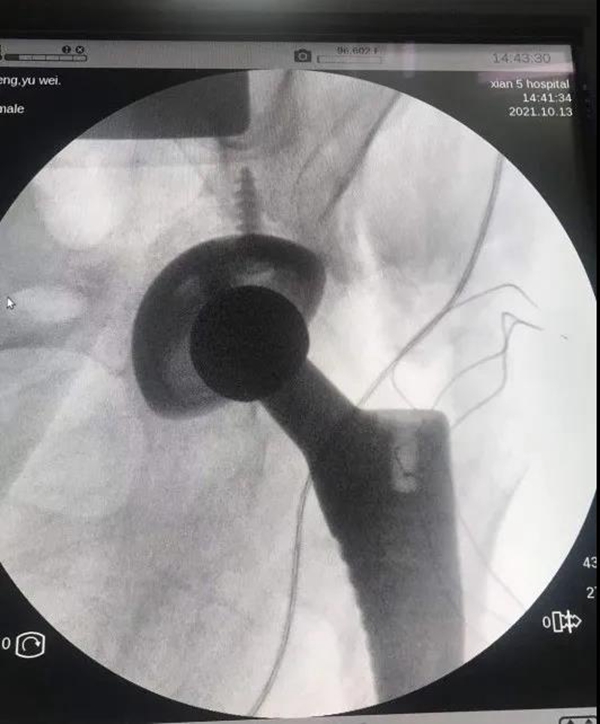

近期腰背部僵硬疼痛伴双髋、双膝疼痛加重,行走困难,听说五院看强直性脊柱炎经验丰富,经病友介绍,前来市五院骨科找贺强副主任就诊。贺强副主任接诊患者后,详细询问患者症状,仔细查体,阅读X线片,发现患者双髋已经严重破坏,几乎没有关节间隙,髋关节活动度也很小。经过全科医务人员认真讨论,决定使用全髋关节置换术,解决患者髋关节疼痛和活动受限的问题。但强直性脊柱炎的全髋关节置换术手术要比普通全髋置换难度大很多,属于复杂初次全髋关节置换手术,对假体的安装精确度要求很高,假体安装角度稍有偏差,就会发生术后脱位。由于患者自身身体条件有限,患者髋臼的尺寸比普通人的髋臼小,很可能最小号的髋臼假体也无法给患者使用。

贺强副主任结合之前参加国际和国内的骨科会议中学习到的先进技术,决定采用3D打印技术为患者解决难题,经过多方联系,最终为患者打印了适合患者的髋臼的等比例模型,通过3D打印的髋臼模型发现患者的髋臼内径仅为44mm,而且髋臼前倾角比常规的大很多。贺强再次组织科里医护人员进行详细讨论,经过周密的术前准备,给患者安排了全髋关节置换手术,带领徐剡副主任医师和崔治国主治医师,成功完成强直性脊柱炎患者全髋关节置换手术,术中测试,人工髋关节十分稳定。患者术后第二天右髋疼痛明显减轻,对术后效果十分满意。